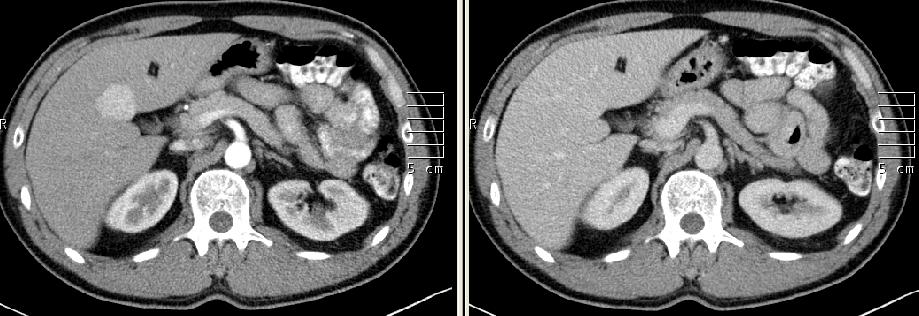

| jelen vizsgálatán artériás fázisban erőteljesen halmozó hepaticus góc (30 mm), vénásban isodens |

| két évvel korábbi CT vizsgálatán ugyanolyan halmozásdinamikájú a góc, de kisebb (20 mm) |